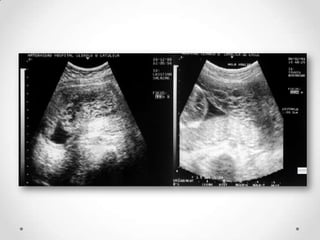

• Ecografía transvaginal.

•   Ecografía pélvica